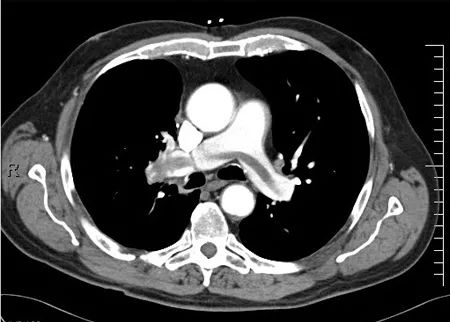

而肺循环系统则是一个高效的运输大队,它负责把氧气丰富的血液从肺部运回心脏,再输送到全身各个部位。这个系统从肺门出发,沿着气道向外延伸,最终将血液送回心脏的左心房。是不是觉得这两个系统就像一对默契的搭档,共同守护着我们的呼吸健康?

肺动脉系统是肺循环系统的重要组成部分,它沿着气道从肺门向外延伸,向下连接下段气道的动脉。这些动脉的壁薄且富有弹性,就像一群优雅的舞者,在肺部跳着美妙的舞蹈。

从肺门开始,动脉逐渐变得肌肉化,直到达到30微米,此时肌层消失。这些小肌肉动脉起着积极控制肺部血流分布的作用,大部分动脉压降都产生在这些小肌肉动脉中。肺小动脉将血液排空,送入广泛分布的毛细血管网,进入肺静脉。肺静脉的壁很薄,它们最终在肺门处与动脉和支气管汇合,出肺进入左心房。